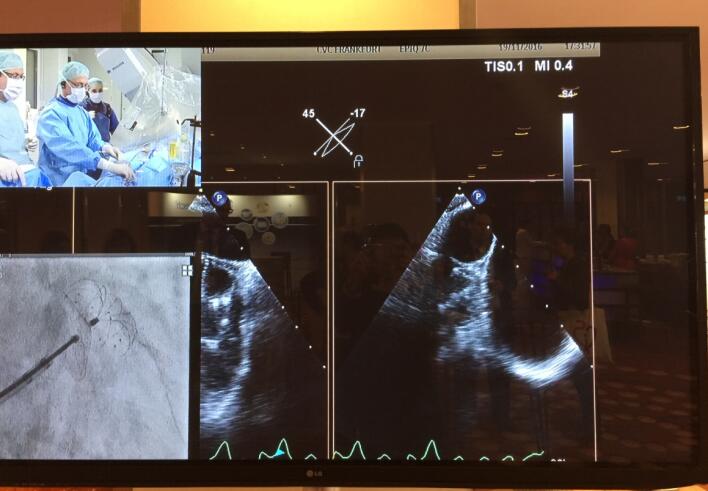

手术直播一直是LAA CSI Focus左心耳专题会议的亮点。本届会议共向现场直播了8台手术,其中两台手术使用了先健科技LAmbre™左心耳封堵器系统。11月19日上午,大会主席,来自德国法兰克福心血管中心的Horst Sievert教授和来自香港的林逸贤医生使用LAmbreTM 左心耳封堵器系统成功完成一例高难度的左心耳封堵手术。

当时,接受该手术的患者已麻醉就绪,超声波影像显示其左心耳形态为多叶型,且左心耳开口尺寸较大。会议现场对该病例的器械选择讨论异常激烈,场内多位专家讨论表示该患者适合使用LAmbre™左心耳封堵器进行封堵,也有部分专家坚持自己的学术主张。对于该病例,主要术者Horst Sievert教授首先尝试使用其他品牌的左心耳封堵器进行封堵,两次植入均出现封堵器无法完全封堵病人左心耳的情况或存在器械脱落的风险。此时,距离手术开始已将近一小时。在此非常情况下,Horst Sievert教授立即发起了与会议现场专家的实时讨论。在对病人的情况进行了详尽的分析,并对现今市面上各品牌的左心耳封堵器械产品的特点和优势进行了讨论后,现场专家一致认为先健科技公司LAmbre™左心耳封堵器独特的小伞大盘设计非常适合多腔左心耳的封堵,对于病患是更为安全和稳妥的选择,能够对其开口尺寸较大的多叶型左心耳进行完全封堵。在更换为使用先健科技公司LAmbre™左心耳封堵器系统后,接下来的手术非常顺利。Horst Sievert教授与林逸贤医生配合无间,先将一枚特殊规格的LAmbre™左心耳封堵器的固定盘送入病人左心耳分支腔内,随后在左心耳开口处释放LAmbre™左心耳封堵器密封盘实施封堵,仅用约十分钟便完成了该例挑战性手术。术后造影显示,病人左心耳封堵完全,无残余分流。当LAmbre™左心耳封堵器被稳当的植入目标位置后,全场爆发出了热烈的掌声。在封堵器未释放前,应全场专家的共同要求,大会破例在现场对该手术过程进行了慢镜头回放,并由林逸贤医生分步骤详细讲解了LAmbre™左心耳封堵器释放封堵的全过程。

图:大会现场手术直播对LAmbre™左心耳封堵器系统的特写

图:LAmbre™左心耳封堵器植入后造影及超声图